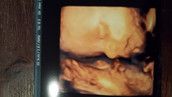

Ich freue mich einerseits schon so und als ich zum ersten Mal das kleine Herzchen schlagen sehen und hören konnte, war ich den Glückstränen nahe... aber die Sorgen machen sich eben immer wieder breit. Bei jedem kleinen Anzeichen (einerseits Unterleibziehen, andererseits ein plötzlicher Wegfall der Übelkeit... usw...) poppt eine Frage in mein Hirn... Geht's dem kleinen Ding in mir gut? Ist etwas passiert?